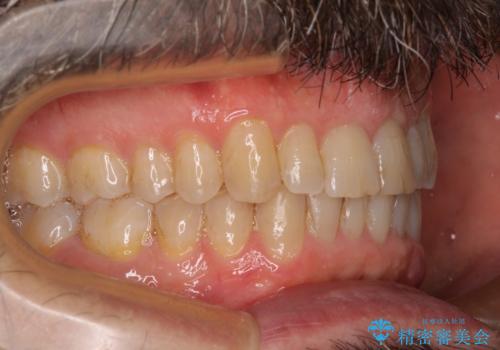

【モニター】前歯のデコボコを治したい インビザライン矯正治療

- 患者様

- 40代男性

- 矯正装置

- インビザライン

- 前歯のデコボコを気にして来院された患者様です。

インビザラインでもワイヤー装置でも対応可能でしたが、仕事の都合で来院回数を減らしたいとのことでインビザラインによる矯正治療を選択されました。

著しく咬合力が強いため、奥歯がしっかりと噛めずに治療が長引くことが懸念されました。

1セット目のインビザラインを使用した際には左右ともに大臼歯が咬み合っていなかったのですが、2セット目できっちりと仕上げることができました。